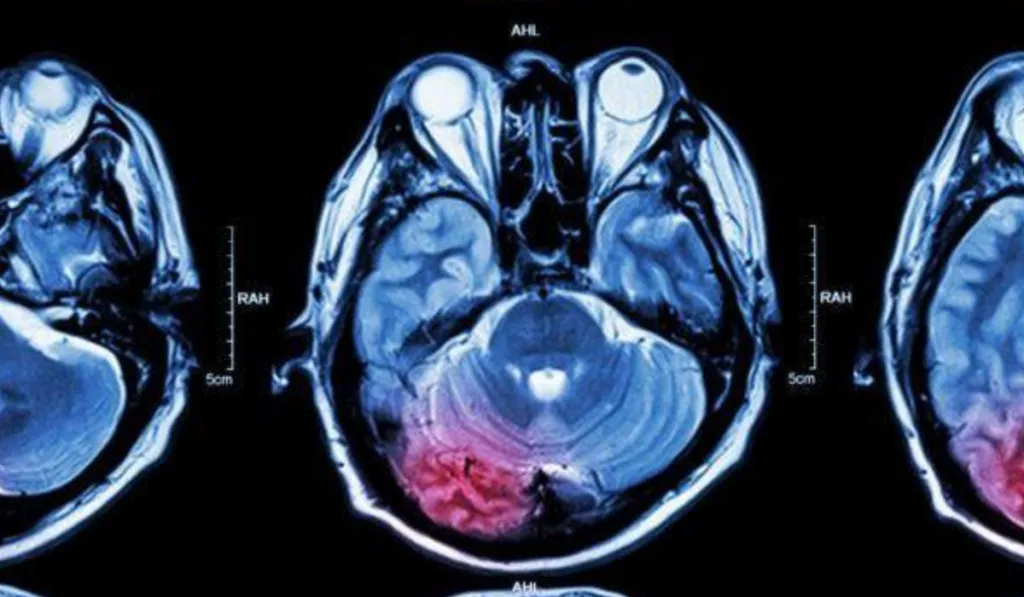

Actualmente, el diagnóstico de estos padecimientos suele implicar procedimientos invasivos como biopsias o múltiples resonancias magnéticas. Este nuevo enfoque propone una alternativa más rápida y menos agresiva para los pacientes.